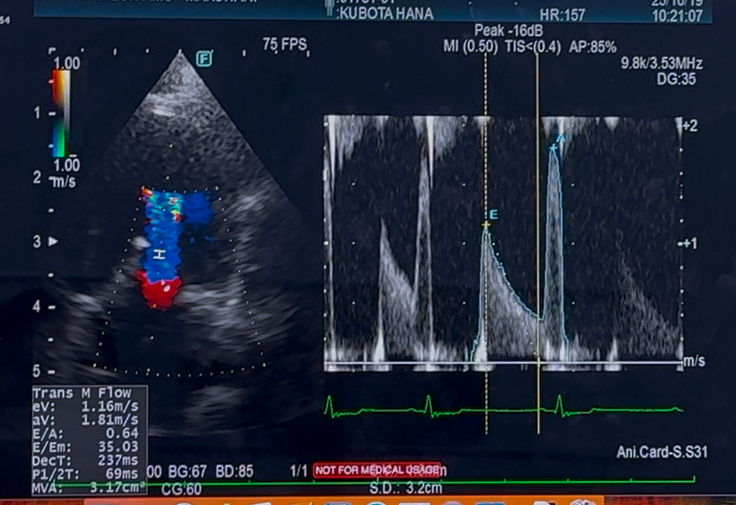

先日心臓手術後2年2ヶ月検診でした

心臓の方は

年齢的なものも相まって少し悪化がみられましたが

今すぐに何かしなければいけないと言う事はありませんでしたが

抗血栓薬は、まだ内服継続となりました